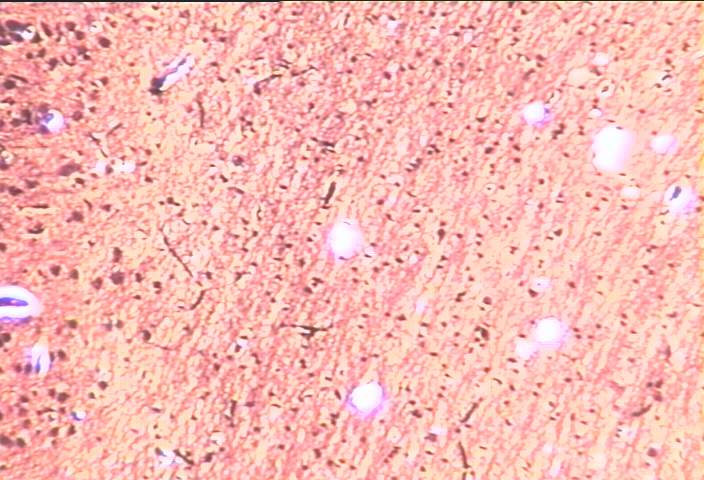

切片位置:大腦皮質

切片倍率:100x

染色方式:silver stain

中倍率 (100x) 下特殊染色 (銀染色) 之大腦皮質 (cortex) 之深層區域與髓質 (cerebral medulla),圖形之左側皮質區域可見染色成棕色之神經細胞,其右方大部分區域多為髓質之構造,由神經纖維 (nerve fibers) 與神經膠細胞 (neuroglia) 所組成。